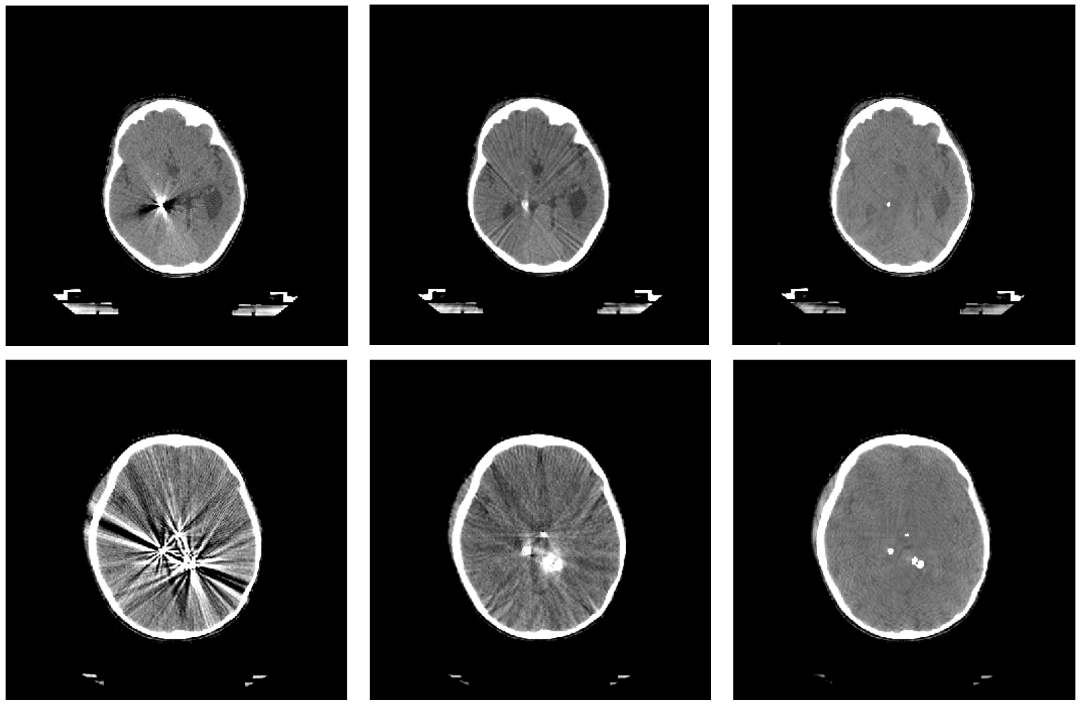

Refer to caption

Figure 2: Example of real shapes of high density objects (above) and shapes generated via proposed pipeline (below).

Figure 2 shows examples of real and generated objects. Using that algorithm for each CT image, we created 30 differently distributed object masks with an approximate depth of 90 slices per sample on average.